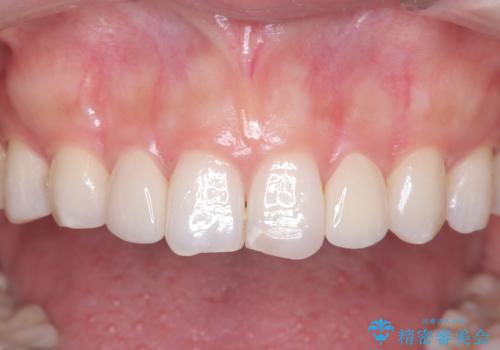

- 歯並びを矯正で整えたあと、上顎左右2番の歯(前歯の横の歯)の「矮小歯(歯が小さい状態)をオールセラミッククラウンで審美修復した症例です。

矯正によって歯並びはきれいに整いましたが、前歯全体のバランスをより自然で美しく仕上げるため、上顎左右2番にオールセラミッククラウンによる審美修復を行いました。

矮小歯はもともと歯が小さいため、削る量を最小限に抑えた負担の少ない治療が可能です。

また、自然な色合いや形になるよう、歯科技工士と連携し、写真を撮影しながら細かく色合わせを行い、周囲の歯になじむよう丁寧に仕上げています。